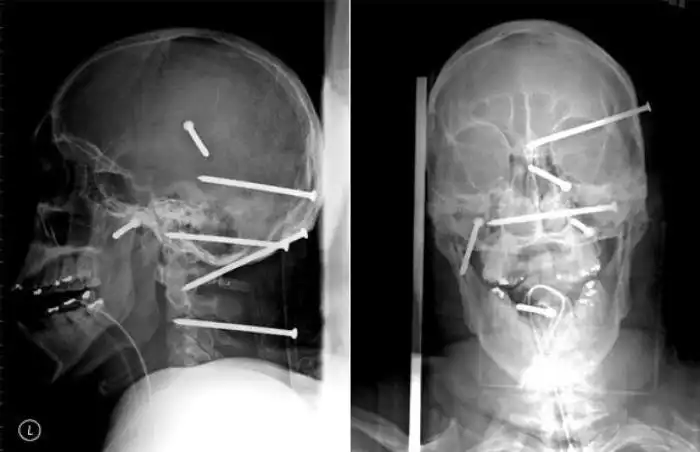

На рентгеновских снимках людей порой можно обнаружить самые необычные предметы, которые находятся в их теле.